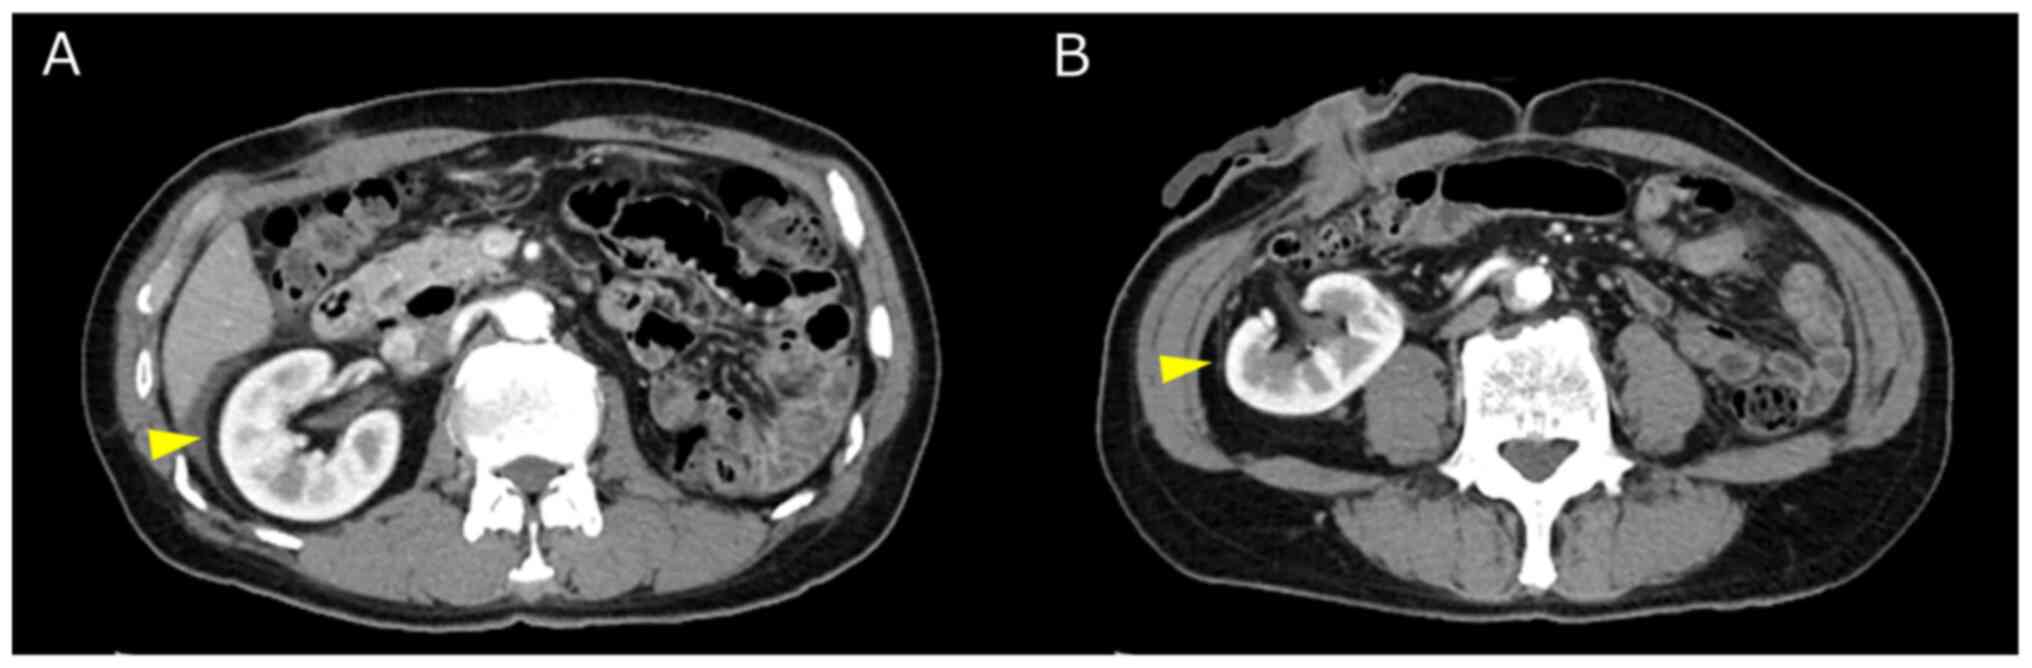

Feasibility of robot‑assisted radical cystectomy in a patient with an ectopic kidney: A case report

An ectopic kidney is a rare congenital defect in which the kidney does not migrate to its normal anatomical position. In the present study, a robot‑assisted radical cystectomy and intracorporeal urinary diversion were performed for a patient with an ectopic kidney. The present study describes the case of a 72‑year‑old male patient who was diagnosed with a bladder tumor by magnetic resonance imaging and cystoscopy. A transurethral resection of the bladder tumor was performed. The pathological examination revealed an invasive urothelial carcinoma. Contrast‑enhanced computed tomography revealed an ectopic left kidney in the upper pelvis. A robot‑assisted radical cystectomy, extended lymph node dissection and intracorporeal urinary diversion were performed. On the whole, as demonstrated herein, a robot‑assisted radical cystectomy with intracorporeal urinary diversion is a feasible approach for muscle‑invasive bladder cancer complicated by an ectopic kidney.